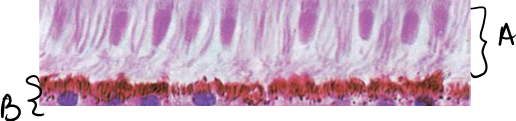

What lymphatic organ is this? What are the stuctures labled A and B?

A

“GALT” falling under “MALT”

A= Lacteals

B= Peyer’s Patch